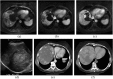

Angiosarcoma is a rare, aggressive subtype of soft-tissue sarcoma with a propensity for local recurrence and metastasis associated with a generally poor prognosis, unless diagnosed early. Given the vascular endothelial cell origin of angiosarcoma, tumours may develop in essentially any organ; however, there is a predilection for the skin where half of all tumours arise, increasing in prevalence with age. The most common risk factors are chronic lymphoedema and history of radiation. We review the most important radiological findings along the spectrum of angiosarcoma from head to toe throughout the body, including uncommon and rare locations. Key imaging features of angiosarcoma across multiple organ systems will be described, as well as the impact on management and prognosis.